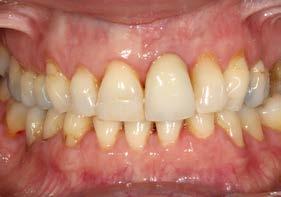

Se presenta el caso de una paciente femenina de 47 años de edad al inicio del tratamiento, quien acude a consulta por dolor y supuración en el incisivo central superior izquierdo. En las imágenes iniciales se observa un diente con un cambio de color llamativo y una supuración espontánea a través del surco gingival (Figura 1). Esta alteración cromática, además de reflejar un problema asociado al diente, afecta de manera significativa la estética del frente anterior, como se aprecia en la imagen de sonrisa (Figura 2).

Tras 6 meses de oseointegración, se procedió a la confección de la prótesis definitiva. En aquel momento, hace 22 años, se eligió un biopilar microfresado y una corona metal-cerámica cementada, que representaban la mejor alternativa para garantizar un sellado adecuado y una estética satisfactoria en el sector anterior. En la actualidad, la opción preferible habría sido una prótesis atornillada con un elemento intermedio (transepitelial unitario) y una corona totalmente cerámica cementada a una interfase. No obstante, es importante contextualizar la decisión en función de la época en la que se finalizó el caso (Figuras 12 y 13).

Estos hallazgos confirman el éxito del procedimiento quirúrgico y de la posterior carga progresiva, con un mantenimiento óptimo de los tejidos duros y blandos a lo largo de más de dos décadas (Figura 15). Los cambios entre el momento inicial y el final del tratamiento son evidentes, especialmente al comparar la imagen intraoral de la primera visita con la tomada a los 22 años, donde la mucosa que rodea al diente 21 —y posteriormente al implante— se muestra engrosada, en buen estado de salud y con una estética destacable. Asimismo, la comparación entre la radiografía inicial, que evidenciaba el fracaso del tratamiento de conductos del diente en posición 21, y la radiografía a los 22 años, que muestra el implante sin pérdidas óseas asociadas, resulta elocuente (Figuras 16 a 19).

Figuras 16 y 17. Comparación entre la imagen inicial —diente con cambio de coloración, encía inflamada y pérdida de grosor— y la obtenida a los 22 años, que muestra estabilidad y salud gingival con el implante.